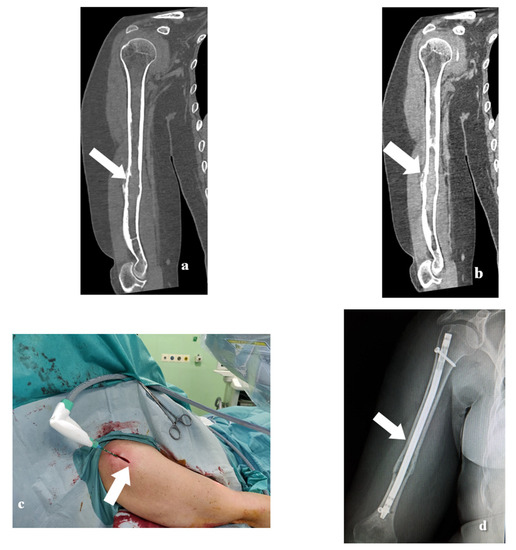

2.2. MWA Technique

2.3. Surgical Technique